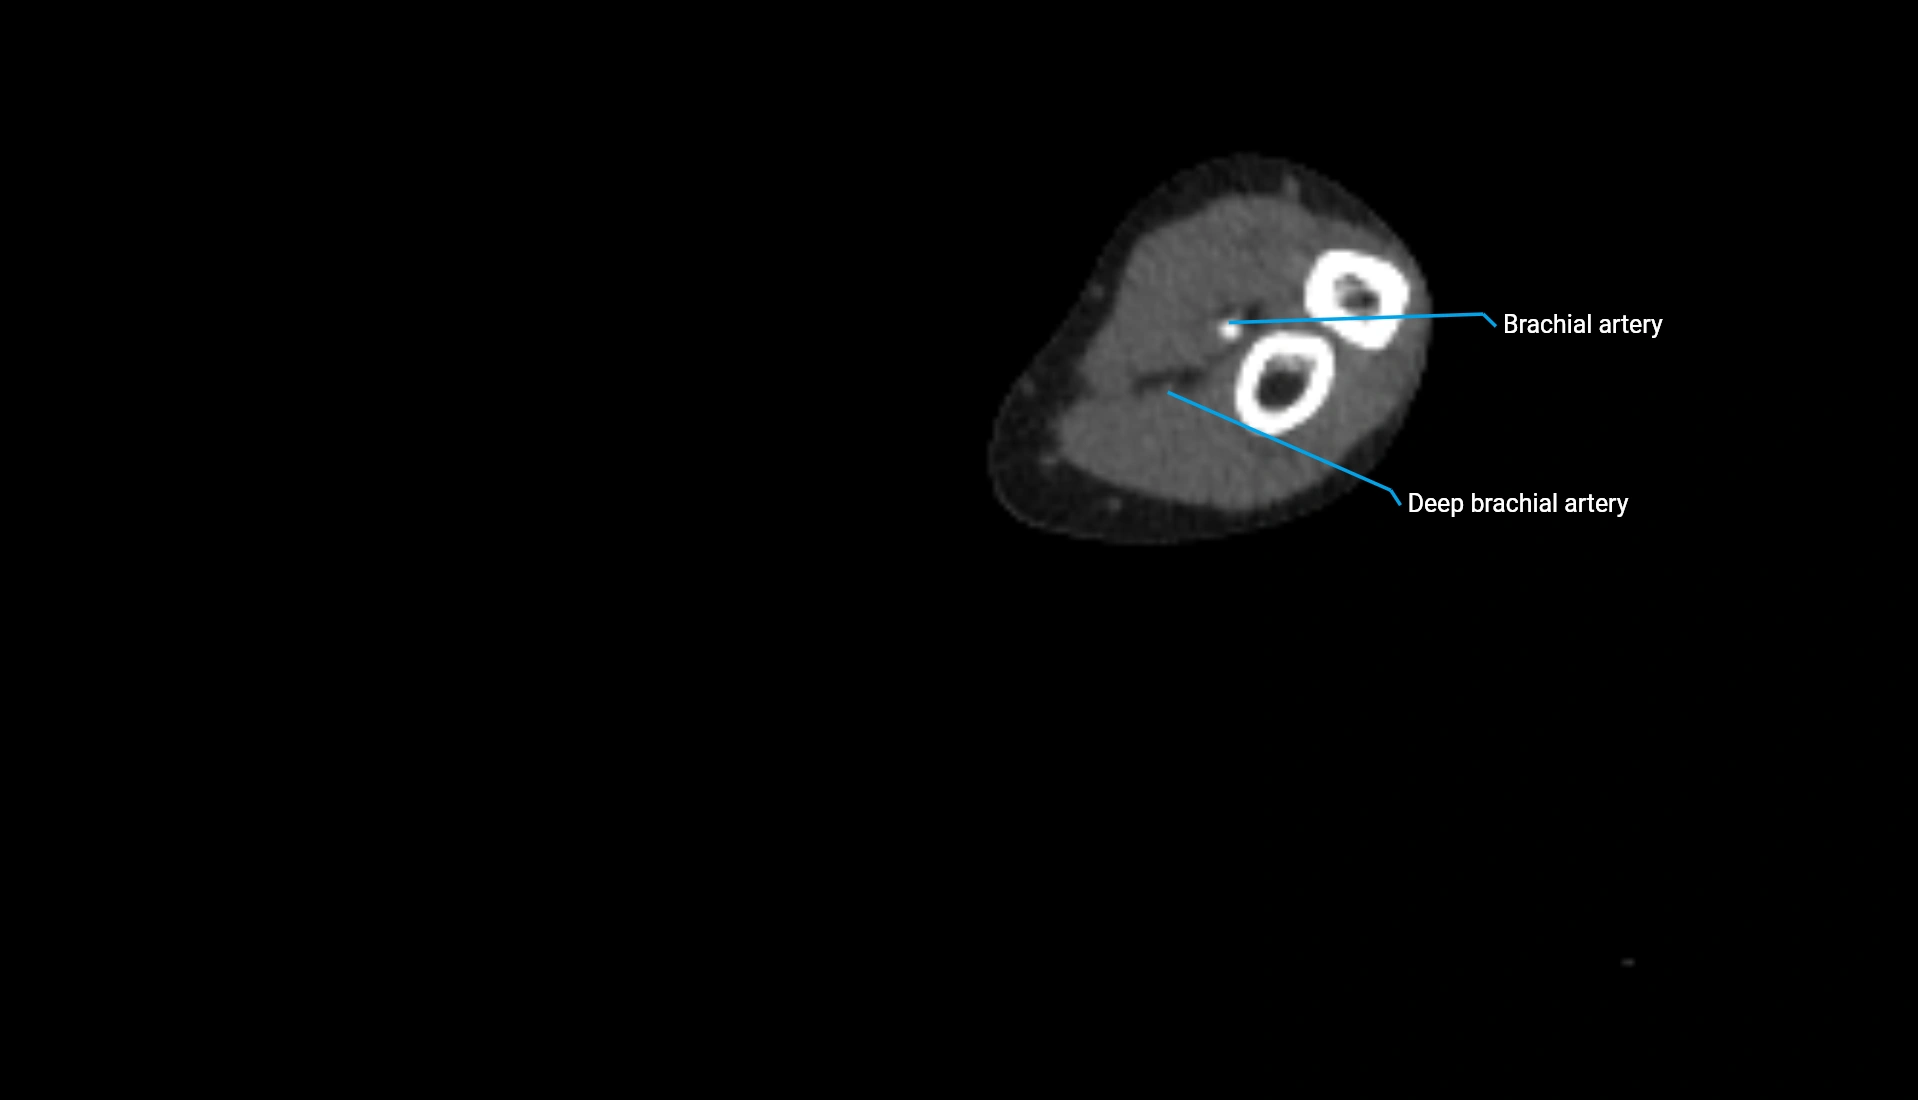

CT Appearance

Non-Contrast CT:

• Cortex: High-density, sharply defined

• Subchondral bone: Dense cancellous matrix

• Articular surface: Smooth concave contour articulating with the capitellum

• Excellent for evaluating bone integrity, alignment, and subtle fractures

Post-Contrast CT:

• Bone: No enhancement

• Joint capsule and synovium: Mild enhancement outlining the joint

• Improves contrast between soft tissues and bony margins

• Useful in detecting subtle joint abnormalities or postoperative changes